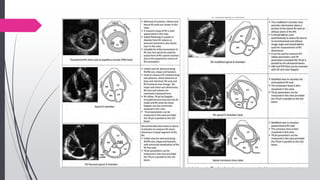

Key views

PLAX & RV inflow

Initial screening of

RA/RV, TR jet

PASX

IVS flattening, TR jet,

RVOT outflow pattern,

PR jet

A4C & modified A4C

RA/RV size, TV, annular

motion, TR jet, IAS

Subcostal

RVH, IVC